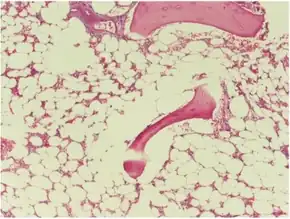

Aplastic anemia caused by temozolomide - Hypocellular bone marrrow with very few erythroid and myeloid cells.[10]